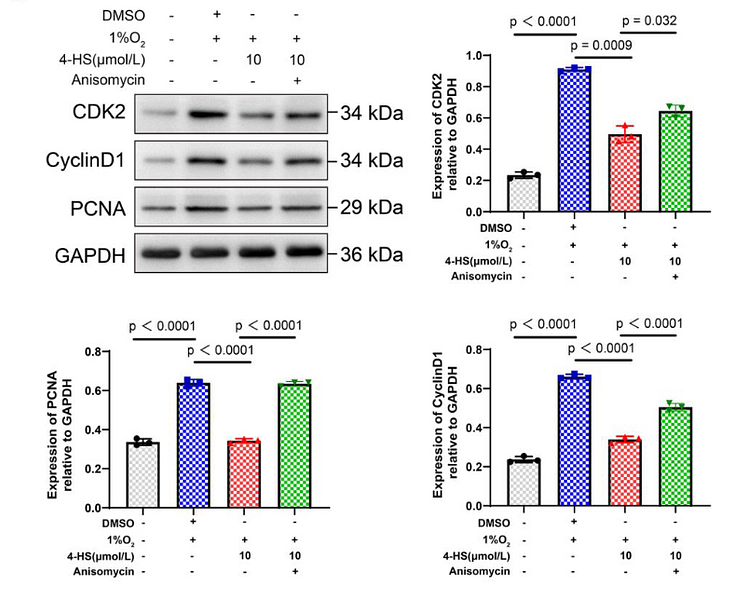

4-hydroxysesamin protects rat with right ventricular failure due to pulmonary hypertension by inhibiting JNK/p38 MAPK signaling

Author: Lingnan Zhang, Xinshun Gu

PMID: 38728253

期刊: Aging-Us

应用: WB

反应种属: Rat

发表时间: 2024 May

-